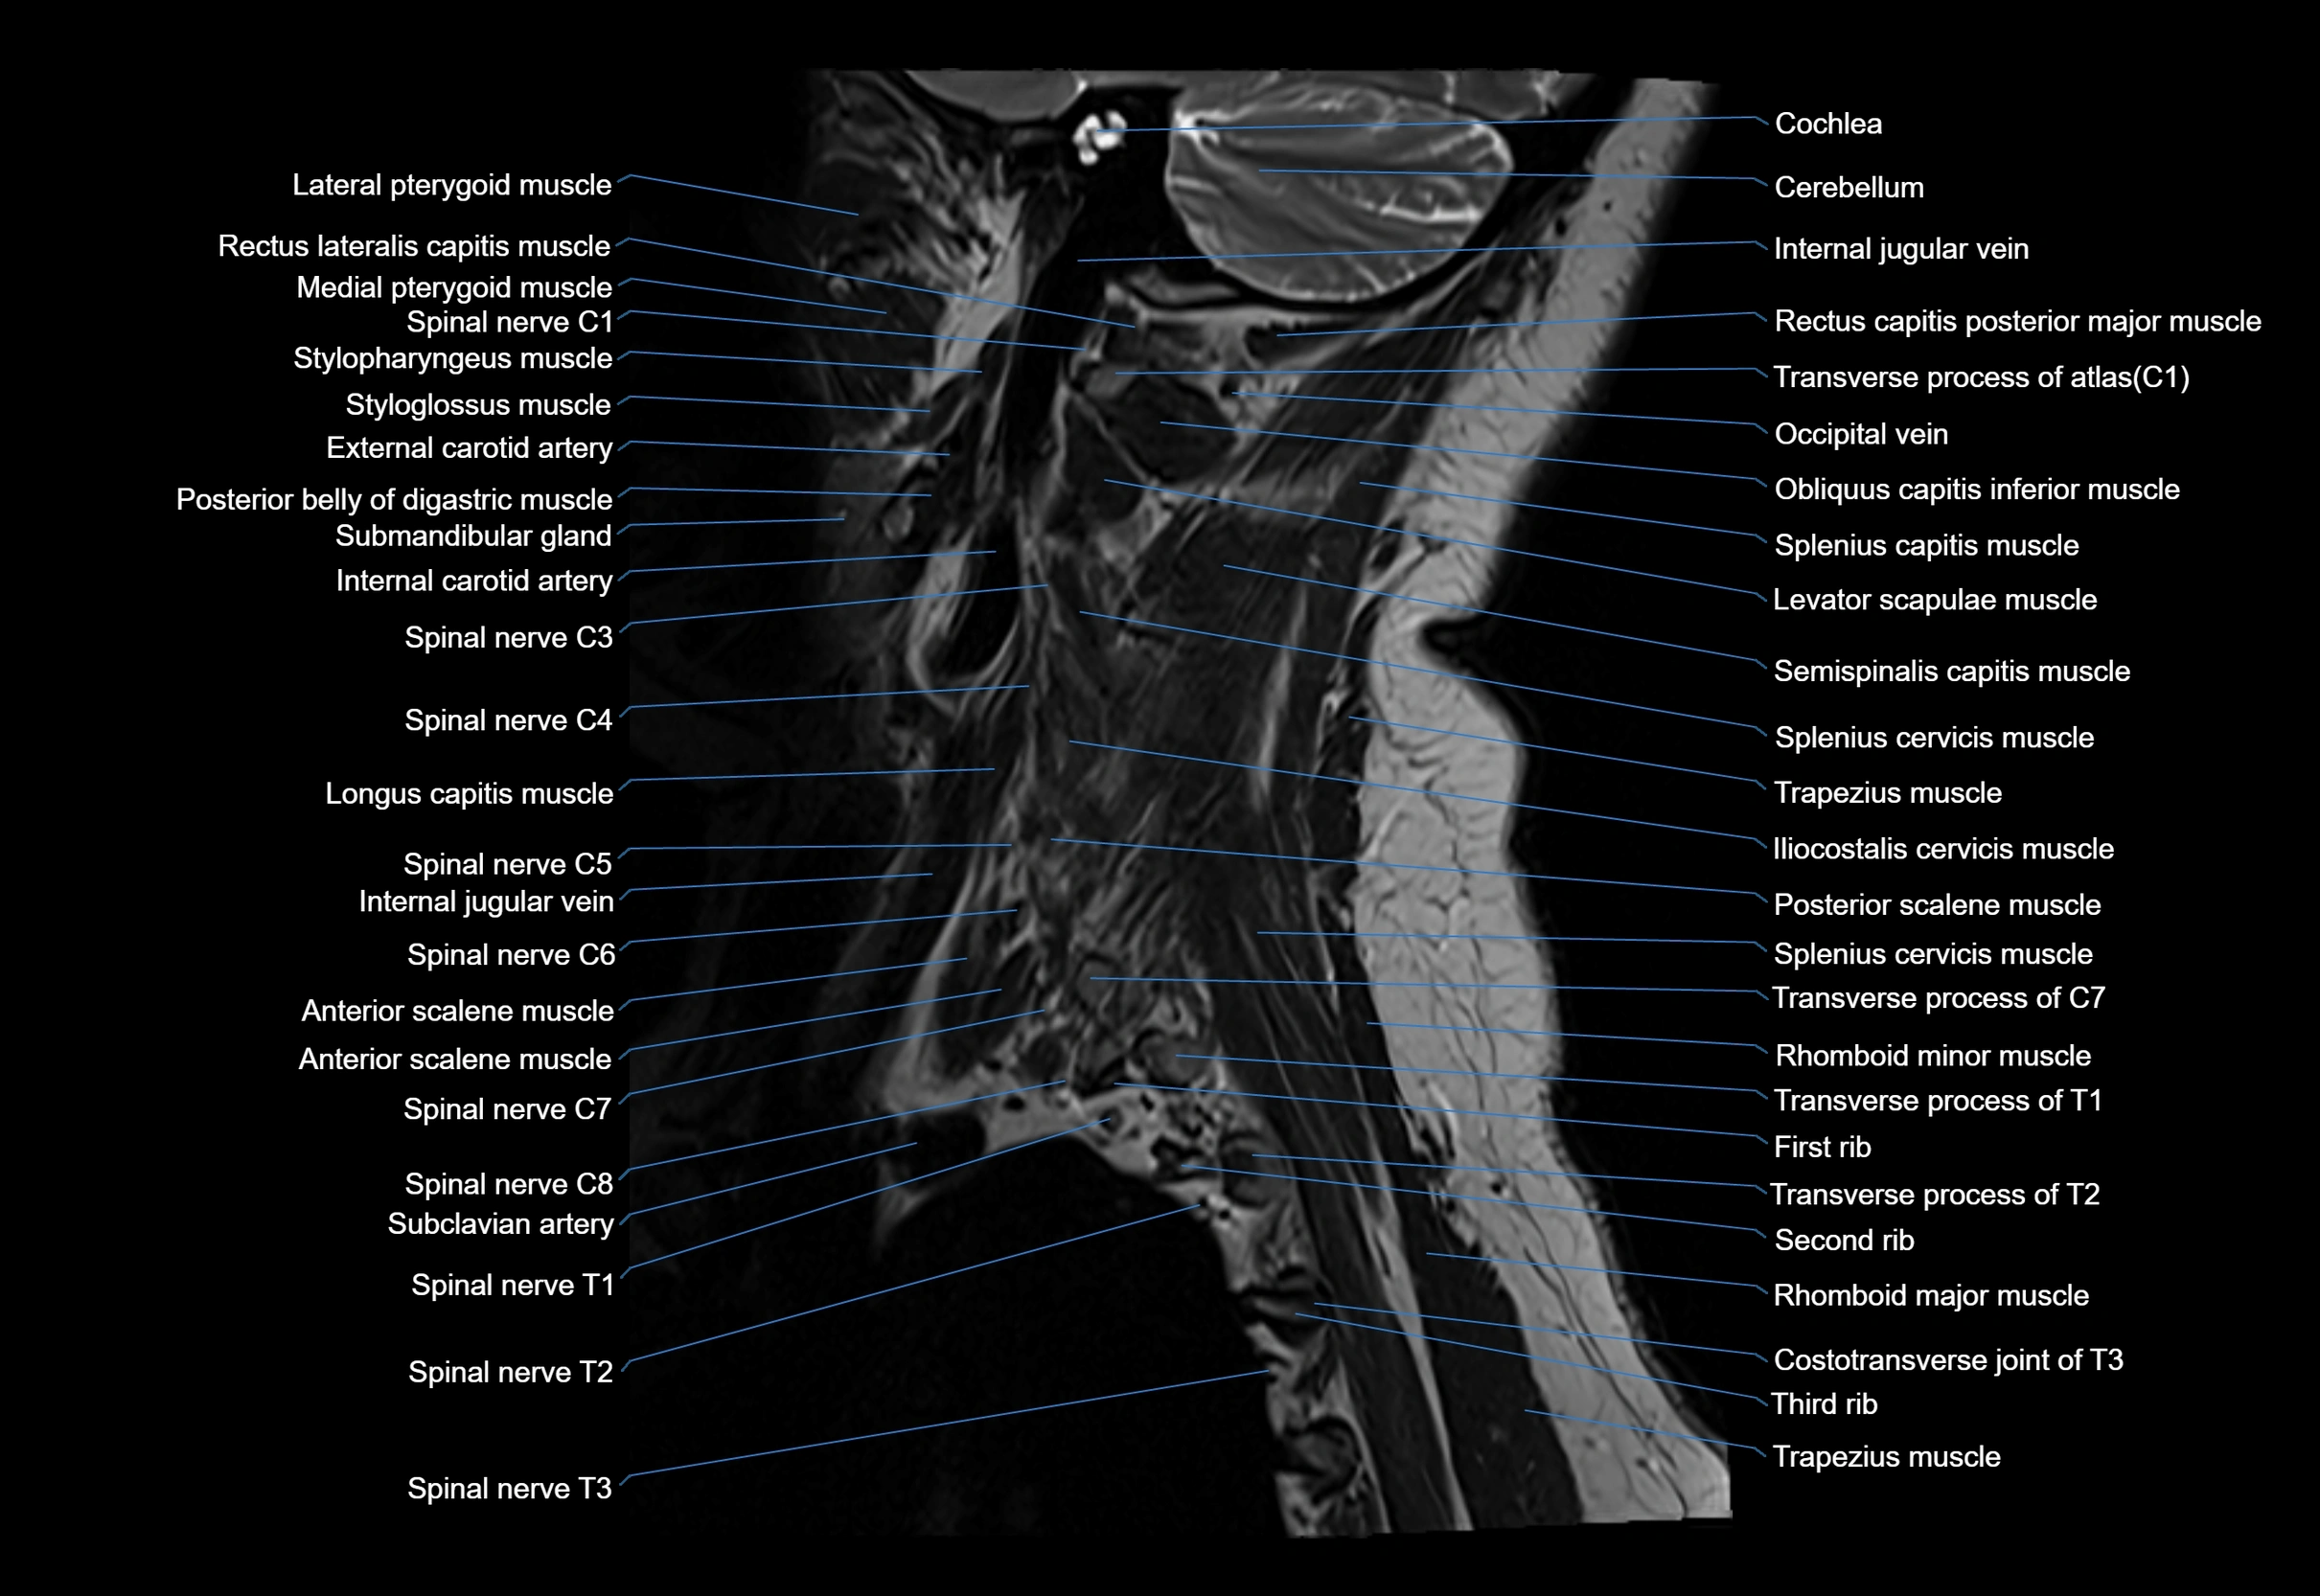

MRI image

image